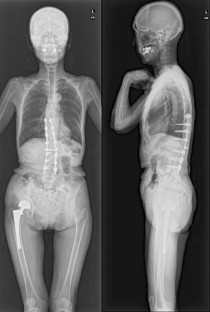

Osteoporotic vertebral fracture (OVF) with nonunion or neurological deficit may be a candidate for surgical treatment. However, some patients do not show improvement as expected. Therefore, we conducted a nationwide multicenter study to determine the predictors for postoperative poor activity of daily living (ADL) in patients with OVF.

The frequency of poor ADL at final follow-up period was 9.1%. In univariate analysis, preoperative neurological deficit (OR, 4.1; 95% CI, 1.8–10.3; P < 0.001), perioperative complication (OR, 3.4; P = 0.006), absence of preoperative bone-modifying agent (BMA) administration (OR, 2.7; P = 0.03), and absence of postoperative recombinant human parathyroid hormone (rPTH) administration (OR, 3.9; P = 0.006) were significantly associated. In multivariate analysis, preoperative neurological deficit (OR, 4.6; P < 0.001), perioperative complication (OR, 3.4; P = 0.01), and absence of postoperative rPTH administration (OR, 3.9; P = 0.02) showed statistical significance.

Preoperative neurological deficit, perioperative complication, and absence of postoperative rPTH administration were considered as predictors for postoperative poor ADL in patients with OVF. Neurological deficits and complications are often inevitable factors; therefore, rPTH is an important option for postoperative treatment for OVF.